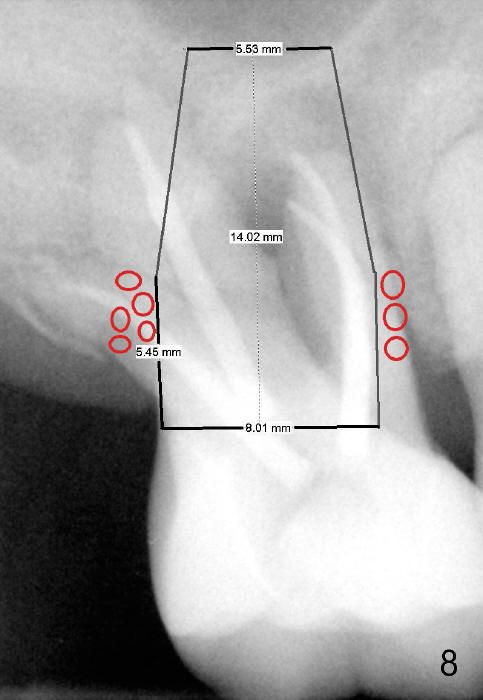

If primary stability is questionable with the bone-level implants mentioned above, a 7x14 mm gingiva-level implant will be the next alternative (Fig.7).  If primary stability is still insufficient, a 7x17 mm (with sinus lift) or 8x14 or 17 mm will be placed (Fig.8).  The larger the implant, the less bone graft is used (compare Fig.7,8).